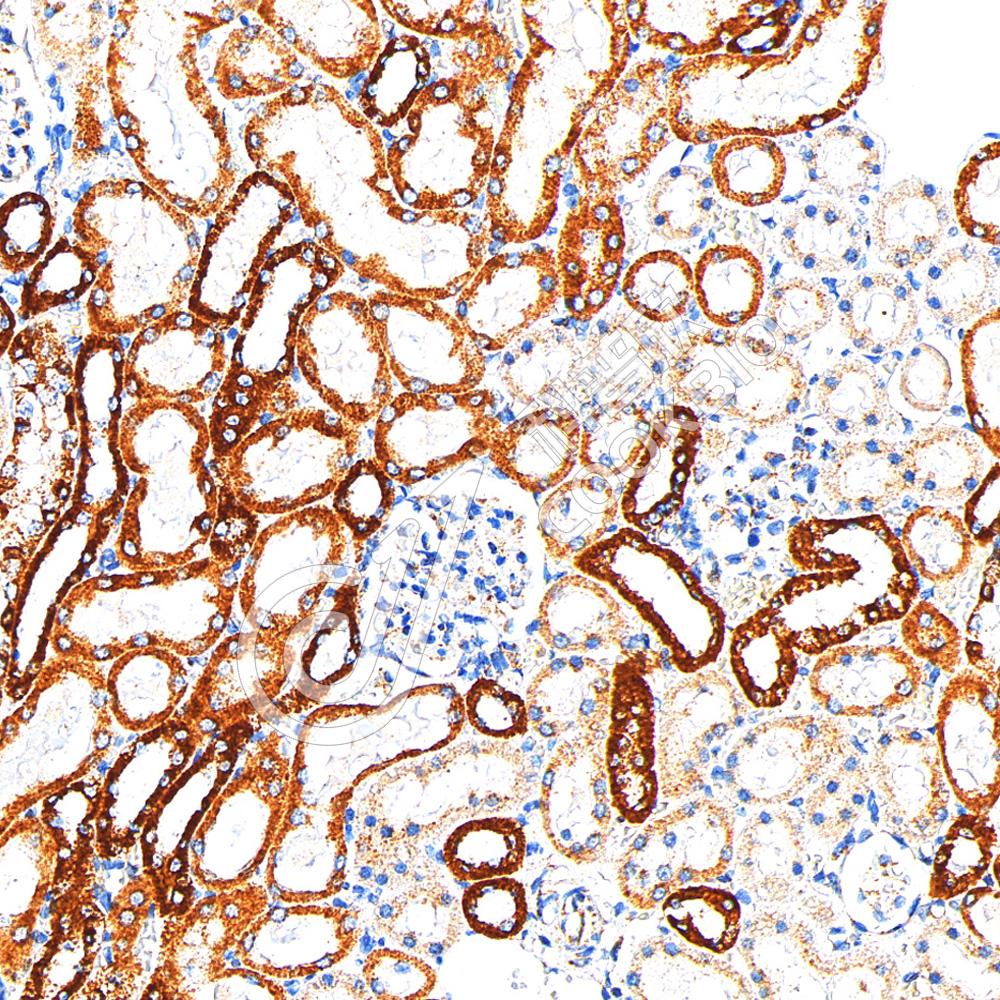

IHC检测COX IV蛋白(货号 K5450039).

样品: 大鼠肾, 4%多聚甲醛 (货号KSG1101) 固定12-24小时.

抗原修复: 柠檬酸抗原修复液(干粉, pH 6.0) (KSG1201), 高压锅均匀喷气计时2分钟.

—抗: 1: 600稀释, 4℃ 孵育过夜.

二抗: S-vision免疫组化多聚二抗(山羊抗兔),即用型 (货号KB3906), 室温孵育20分钟.